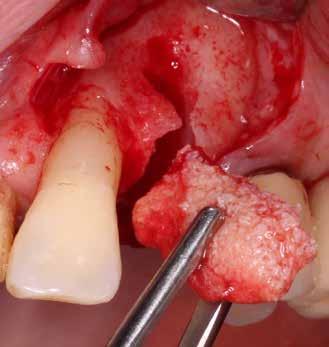

kép). A bemutatott esetben Nobel Replace CC 4,3x13mm implantátumot helyeztünk be, amely a bukkális oldalon direkt kontaktusba került a megmaradt foggyökérdarabbal (7. kép). Az alveolus oldalfalai és a körszimmetrikius implantátum közötti hézag kitöltésére bovin eredetű xenograftot (Creos S xenogain) használtunk (8. kép). A hasonló

5. a–e képek: Részleges extrakció. 4. a–c képek: A fog dekoronálása.

6. kép: Implantátum-ágy preparáció. 7. a–b. képek: Implantátum behelyezés. 8. kép: A behelyezett implantátum. 10. a–b képek: Azonnali ideiglenes korona készítése. 9. kép: Megfelelő primer stabilitás.